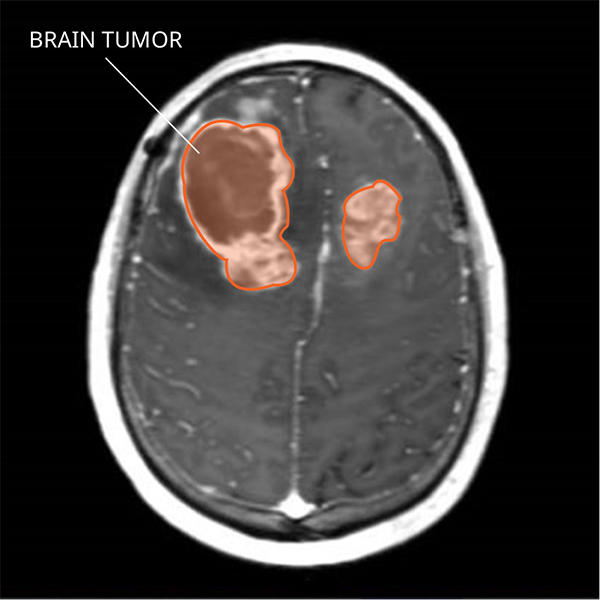

Hình ảnh khối u não (Ảnh: National Cancer Institute)